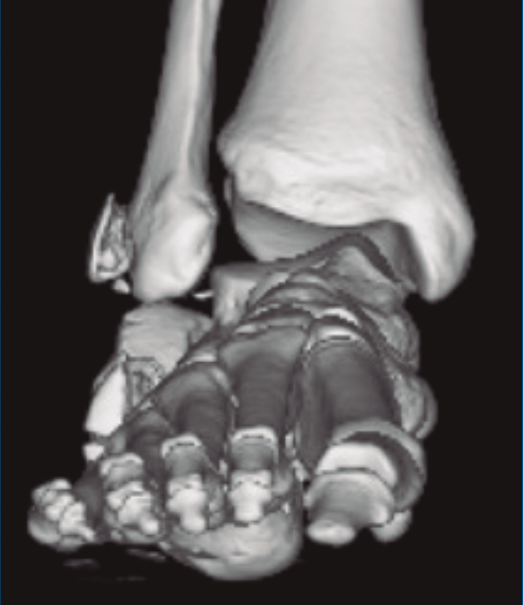

A su llegada a urgencias, se inmovilizó con férula posterior de yeso tras no conseguirse la reducción cerrada (Figuras 7 y 8). Debido a la patología asociada, subsidiaria de tratamiento quirúrgico de urgencias (artrodesis de L2 a L4 con tornillos transpediculares, por parte de neurocirugía), se decide demorar eñ tratamiento definitivo de la fractura luxación de calcáneo 2 semanas, hasta conseguir una mejoría en el estado de las partes blandas.

Figura 8. Radiografía anteroposterior de tobillo, inclinación lateral del astrágalo, ocupación del espacio subperoneo, fractura maléolo peroneo y apertura de sindesmosis.